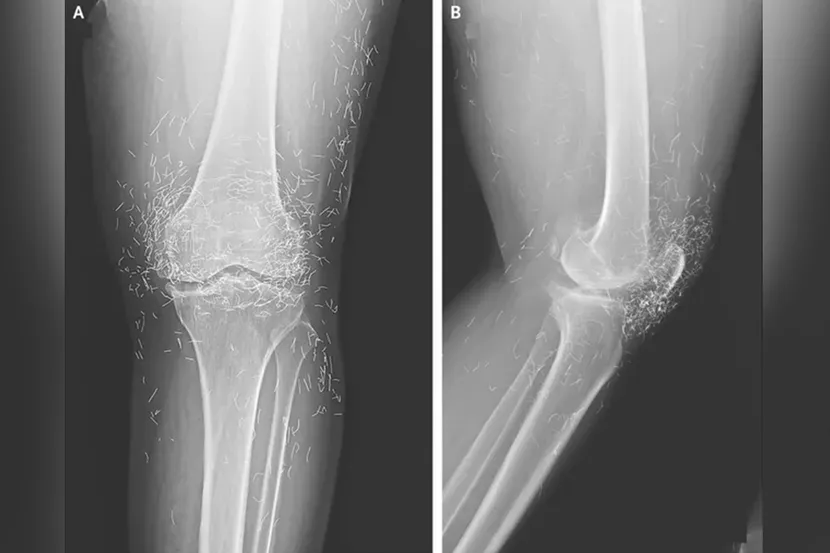

Photo: The New England Journal of Medicine

An X-ray exam revealed a thickening and hardening of the inner part of the tibia, bony growths in the knee, all common symptoms of osteoarthritis – but also hundreds of tiny gold threads embedded in the tissue around the knee. Doctors warn that gold thread acupuncture has no scientifically-proven benefit for the patient, but comes with many known risks. The tiny threads can cause cysts, migrate into the body, and damage surrounding tissue, but they can also make potentially life-saving MRI scans impossible because of the risk of metal displacement and blood vessel damage.